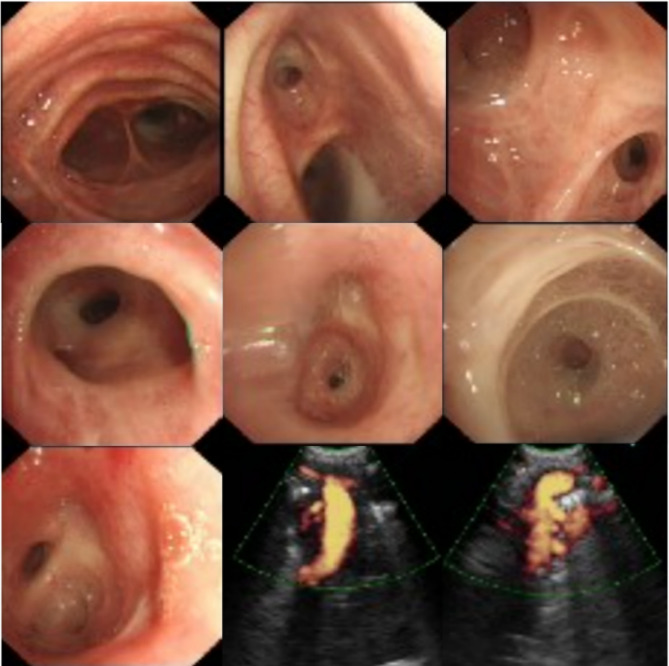

Methods: This case report describes a middle-aged woman who presented with chronic cough, expectoration, and wheezing. She had been misdiagnosed with chronic obstructive pulmonary disease (COPD) at a local hospital for an extended period and was subsequently referred to our institution for fiberoptic bronchoscopy, which confirmed the diagnosis of MKS. By reviewing the literature via PubMed, we conducted a retrospective analysis of 29 previously reported cases of MKS, including the present case, totaling 30 cases (21 males and 9 females), predominantly middle-aged and elderly individuals.

Background: Tracheobronchomegaly, also known as Mounier-Kuhn syndrome (MKS), is a rare congenital condition characterized by significant dilation of the trachea and main bronchi along with an abnormal wall structure. Diagnosis can be confirmed through computed tomography, pulmonary function tests, and diagnostic bronchoscopy. Currently, there is no curative treatment for MKS; thus, symptomatic and supportive care remain the primary therapeutic approaches. Early diagnosis, effective infection control, and individualized management are crucial for improving patient outcomes.